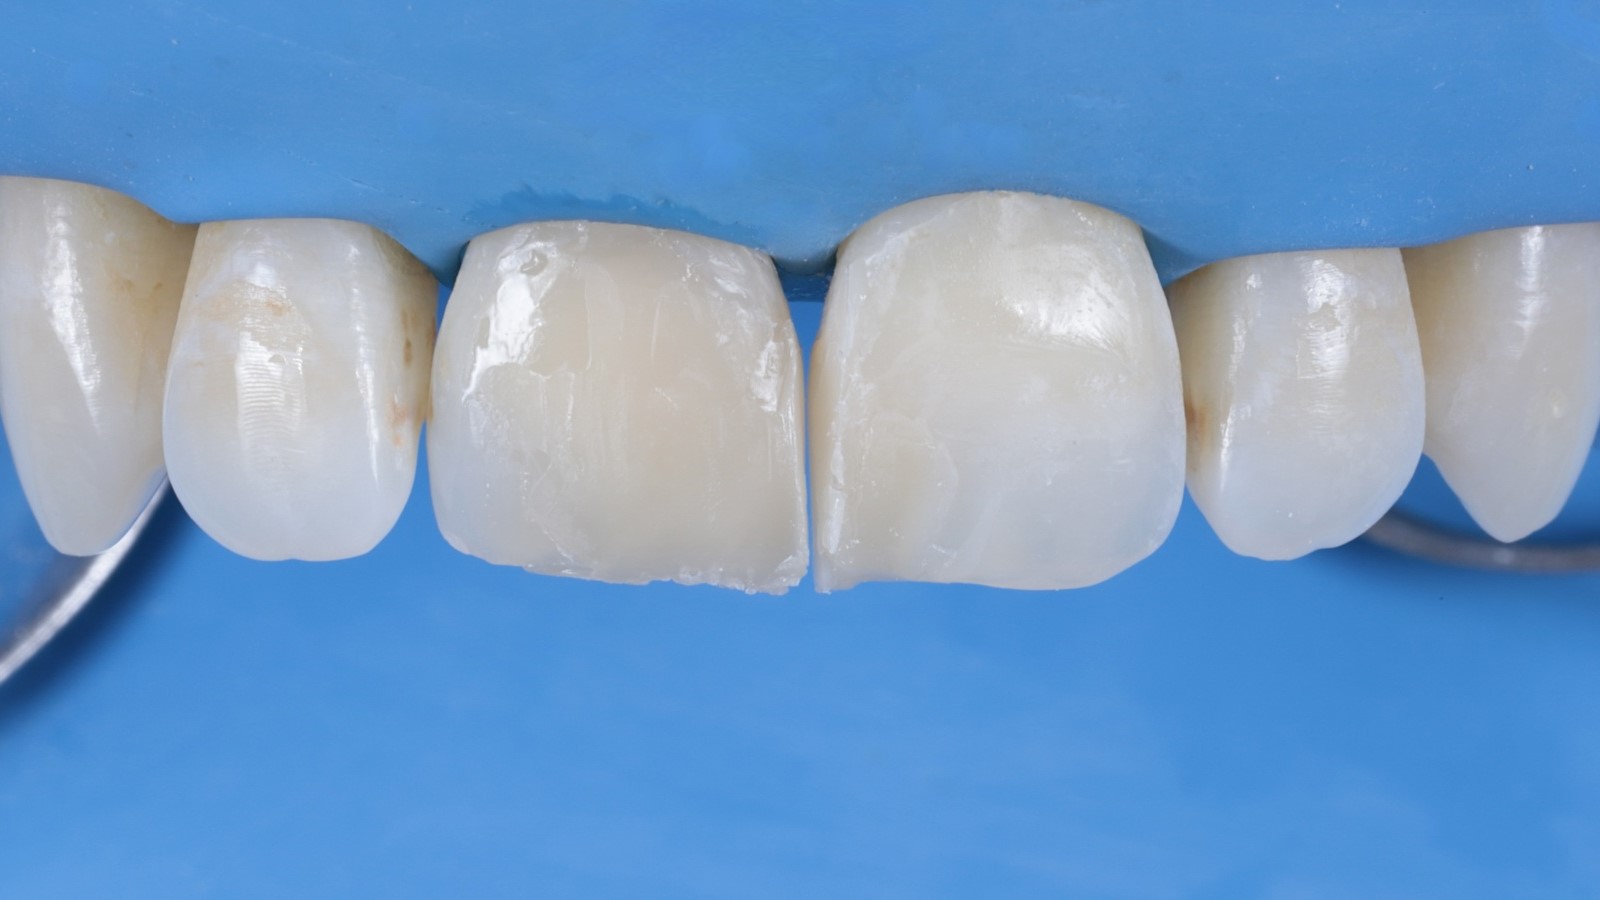

Venus Pearl MEDIUM was used to reconstruct the teeth in a single-shade layering technique. This approach can speed up the restorative procedure and significantly shorten the treatment time.

After reconstruction of the teeth with composite the restorations were ready for finishing to refine the shape.

The restorations were polished while still under the dental dam.